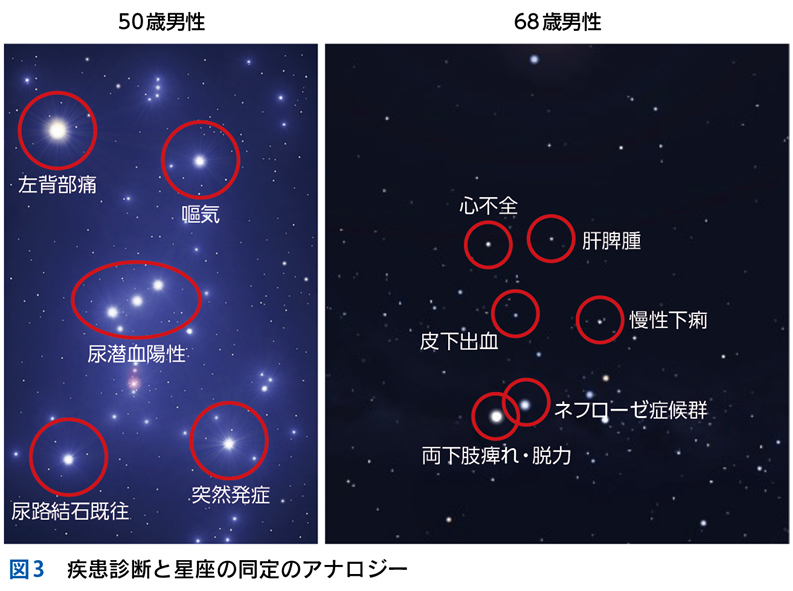

▶ フレームの広さを決めるのは,定義された問題の“yield”である。yieldとは「産み出す」というような意味で,定義された問題がどれほど診断に資するかによって,問題のyieldが高い(high yield),低い(low yield)という使い方をする。high yieldな問題によるフレームは狭く,可能な診断の数を大きく絞り,診断をぐっと近づける。言い換えれば,ある診断(の一群)に対して特異度が高い。一方で,low yieldな問題によるフレームは広く,鑑別診断を意味のある数に絞ることに役立たない(図3)。

▶ 症例によっては,ここまで述べたような条件を満たす問題を複数定義できることがある。この場合は,それぞれの問題が描くフレームが重なり合うところに診断があると考えるとよい(図3)。